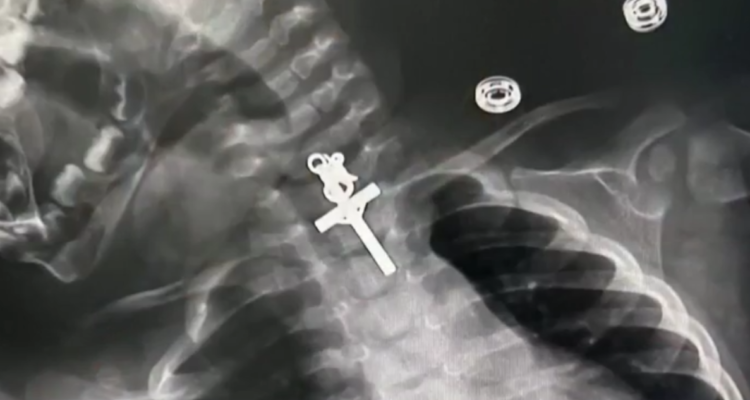

Gracias a una radiografía realizada en el centro hospitalario donde la niña fue atendida, pudieron localizar la cruz en su tórax, más específicamente en su esófago.

Bebé es operada de urgencia en Perú tras tragarse un crucifijo de metal: se le alojó en el esófago